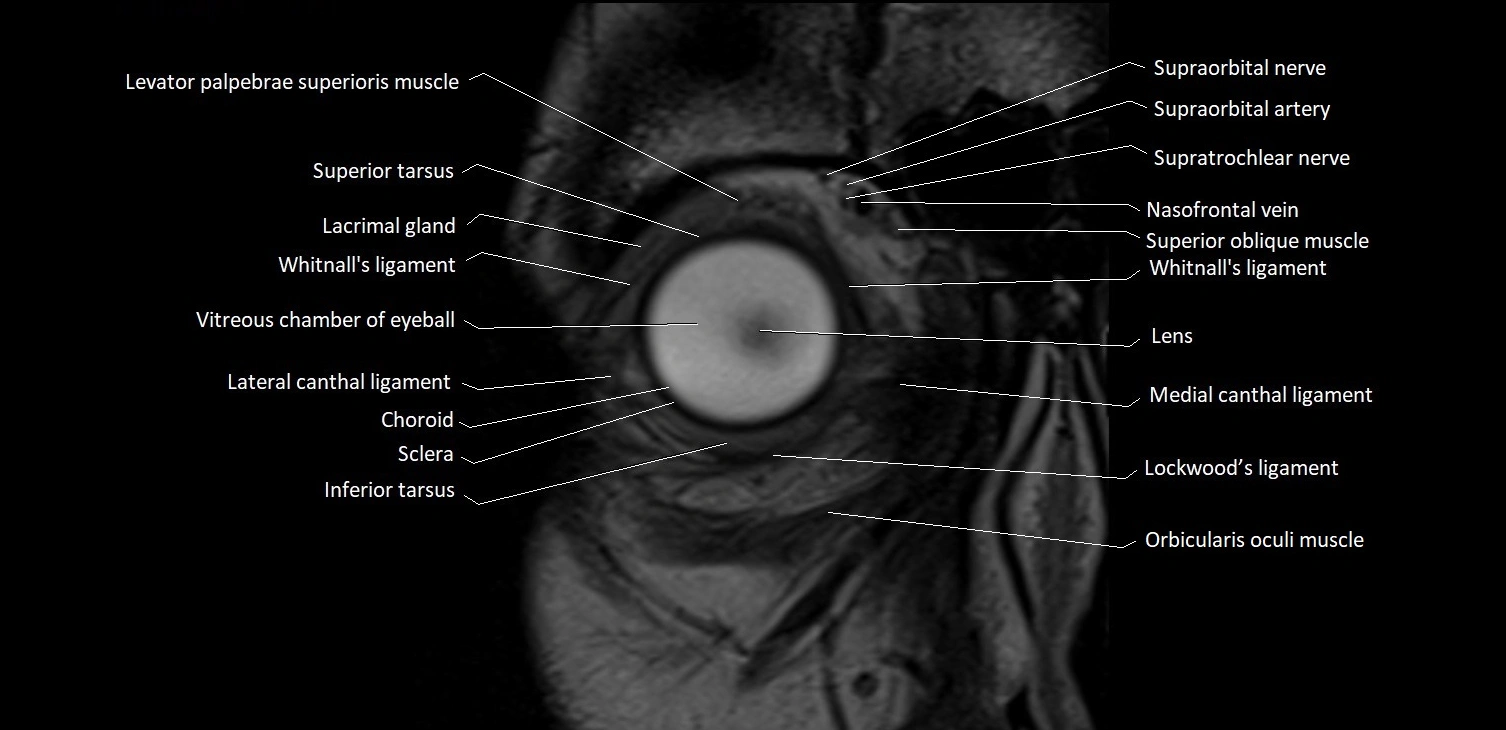

- Levator palpebrae superioris muscle

- Superior tarsus

- Lacrimal gland

- Whitnall's ligament

- Vitreous chamber of eyeball

- Lateral canthal ligament

- Choroid

- Sclera

- Inferior tarsus

- Medial canthal ligament

- Lockwood’s ligament

- Orbicularis oculi muscle

- Supraorbital nerve

- Supraorbital artery

- Supratrochlear nerve

- Nasofrontal vein

- Superior oblique muscle